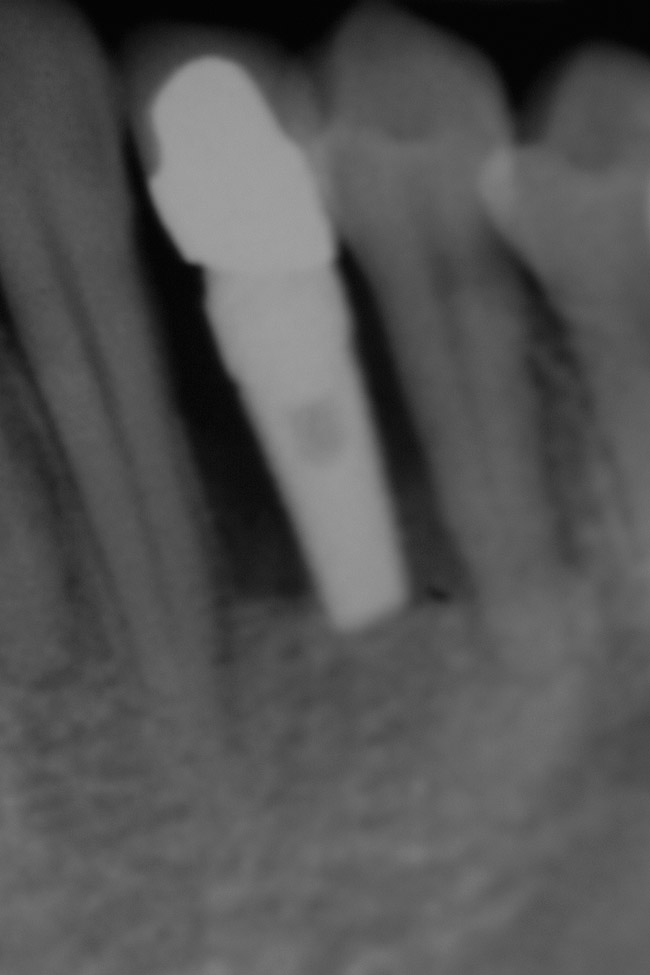

Figure 23  Postoperative radiograph of zirconia abutment.

Figure 23